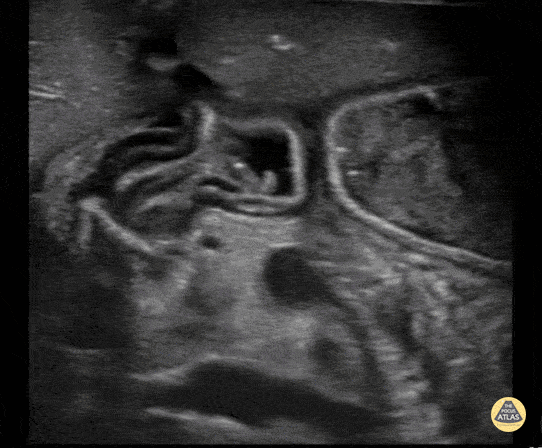

14 year old male presented with scrotal swelling, POCUS identified a hernia into the scrotum. This clip shows normal testicles along with bowel in the scrotum. Contributor: Zach Boivin, MD, @ZachBoivinMD